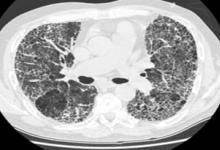

Several studies were reported at EULAR2023 about Takayasu’s arteritis (vasculitis), a very rare large vessel vasculitis that occurs in young individuals.